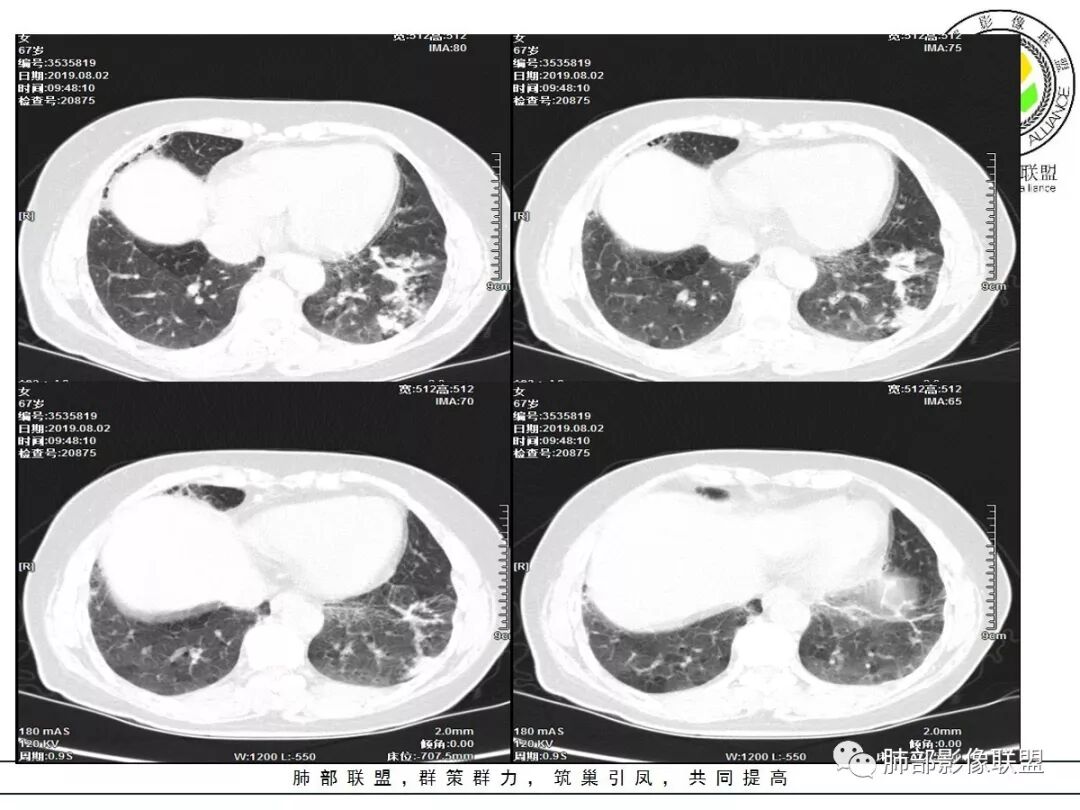

1.老年女性,咳嗽气短2月余,伴发热。病程较长,抗炎疗效不佳。

2.左肺下叶片状影及多数有边界的结节影,较散,多形性,密度不均(注意许多老师提到这个特点还是比较明显的)。左肺下叶体积未见缩小。

3.病灶强化比较明显。

4.左下叶支气管壁增厚,管腔不均匀狭窄,没有堵塞

5.肺门纵隔见增大钙化淋巴结。提示曾经存在慢性病损可能。

1.前述特点除强化外都还是很容易让人首先想到肺结核的可能性。结核是常见病。注意肉芽肿明显的结核灶可以观察到强化。

2.淀粉样变性病变支气管改变一般会更广泛,较少出现单叶肺的如此大片影。

3.腺癌不大会出现较散的腺泡样结节影,更不会出现如本例的支气管改变。增大钙化的淋巴结也很难相互关联。

4.相关支气管未见腔内结节及阻塞,女性患者,鳞癌的可能性更小。